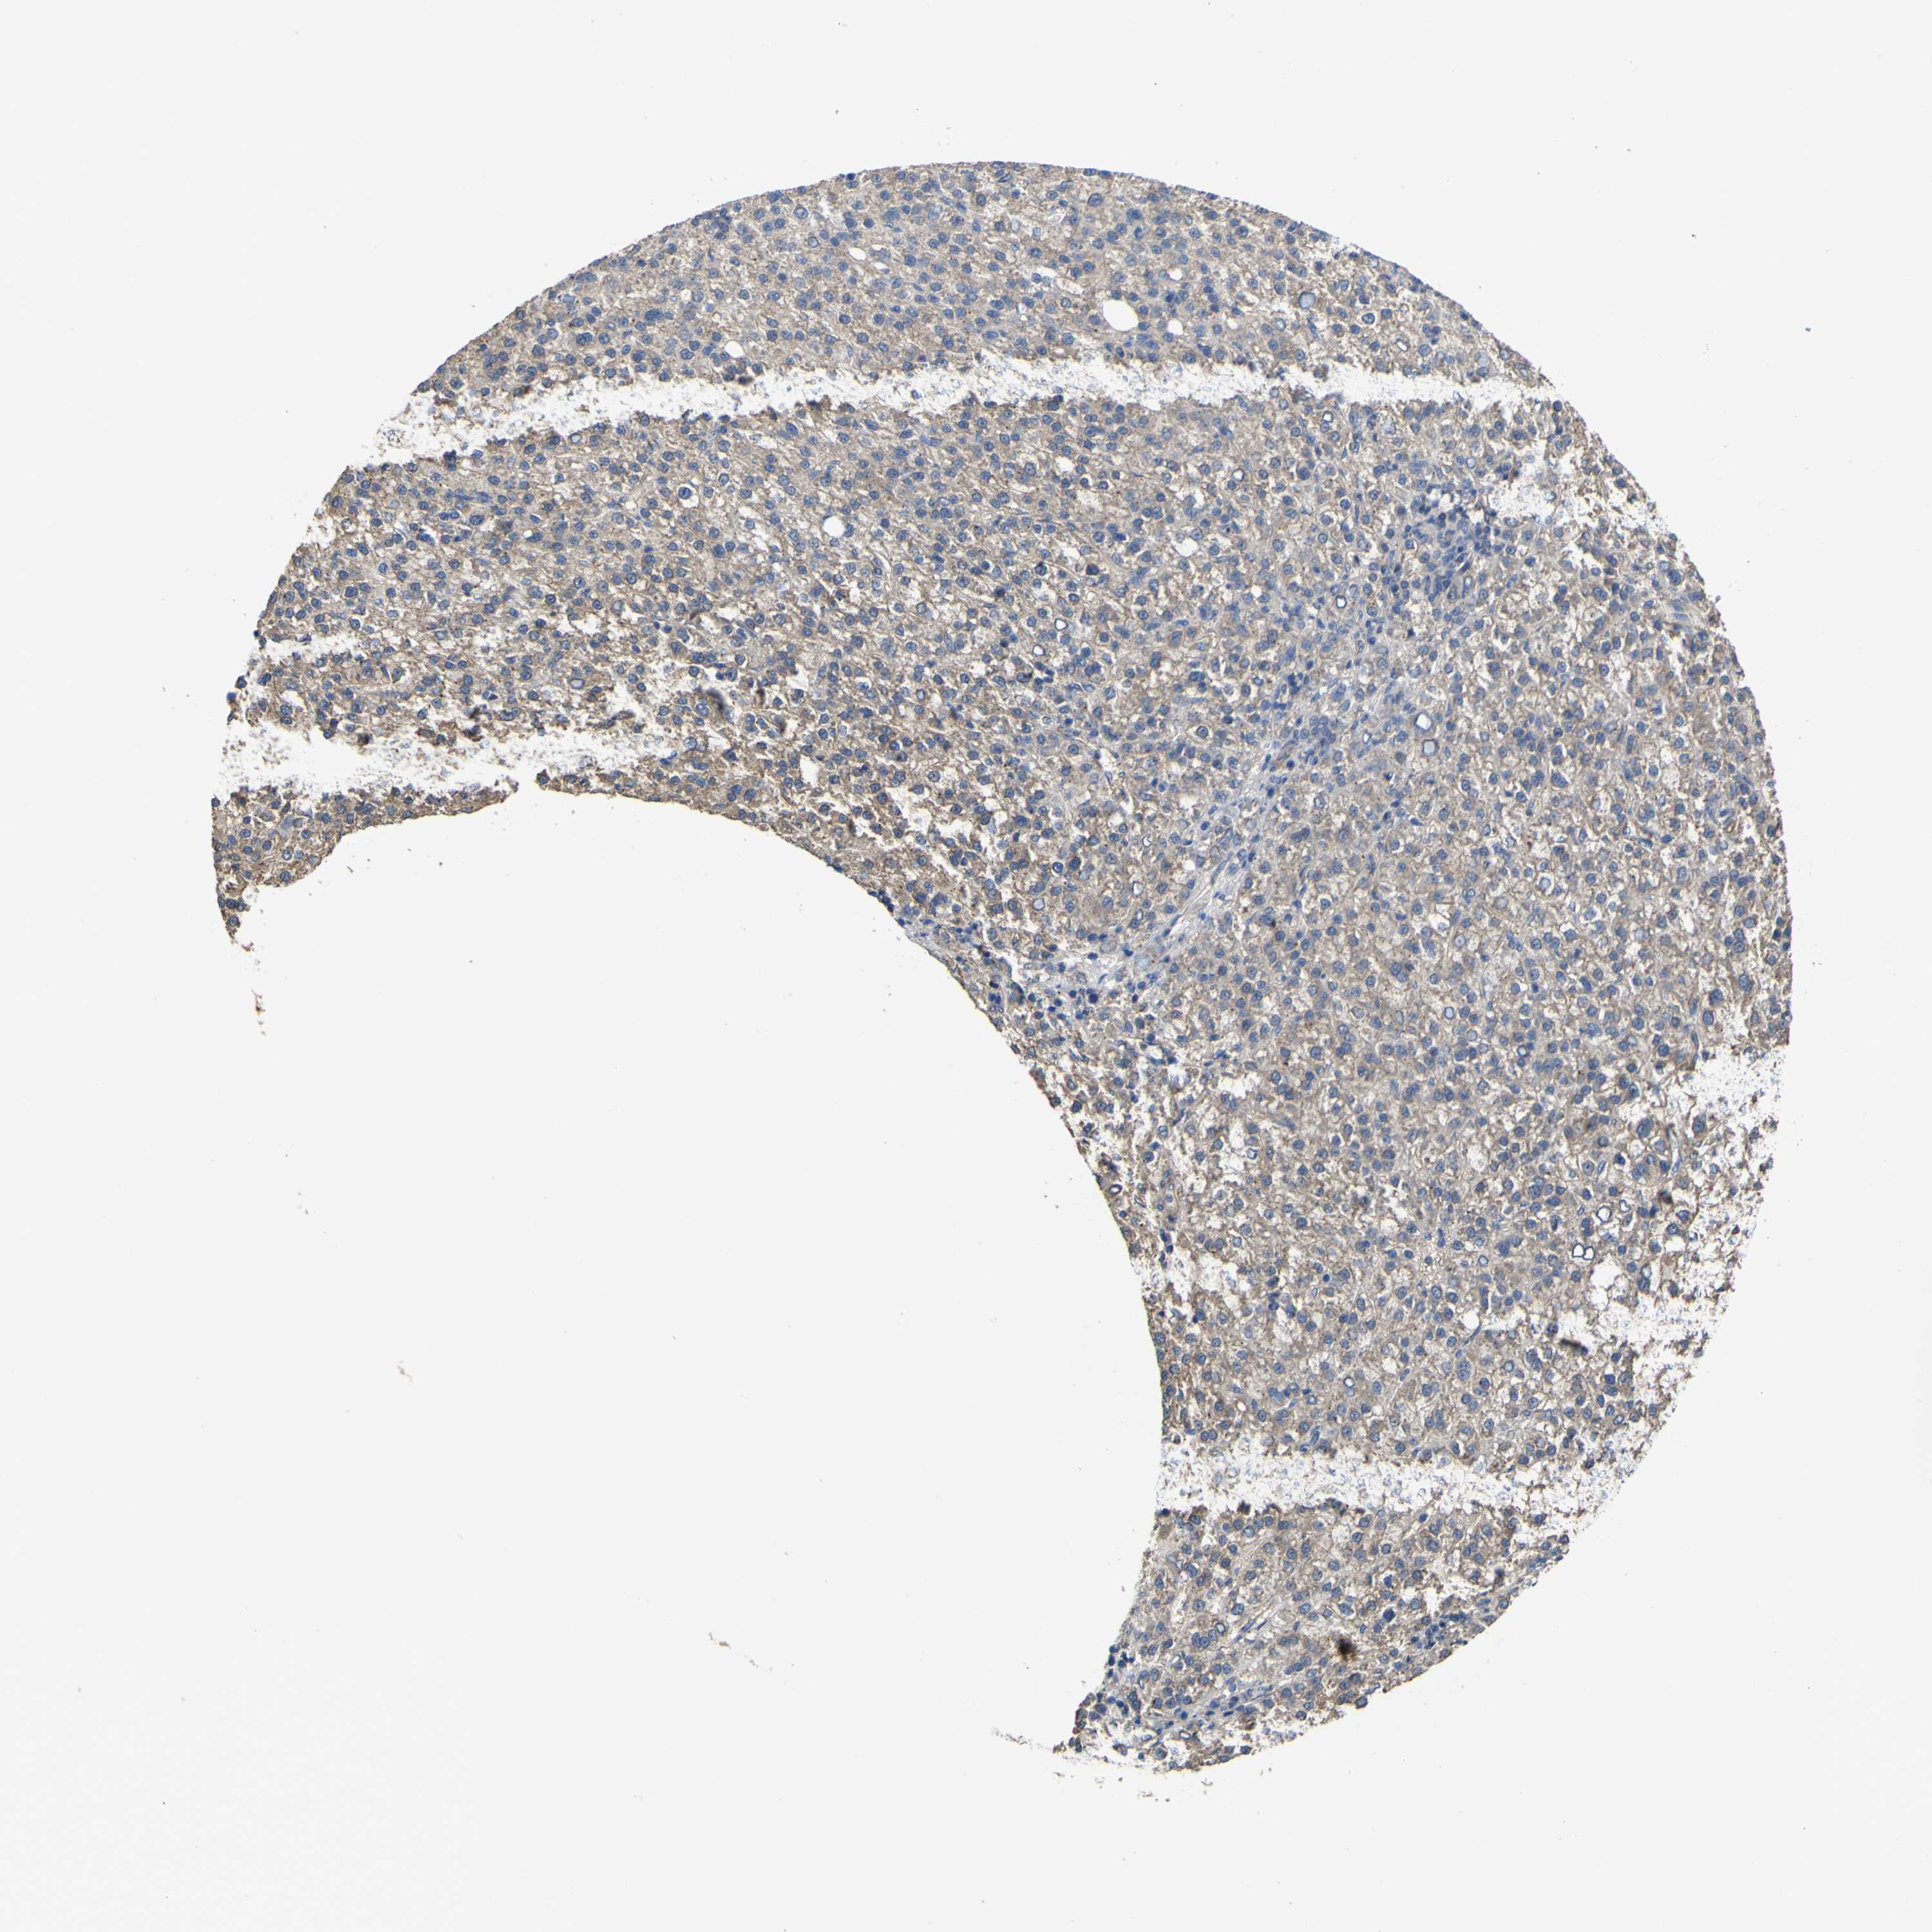

LIVER CANCER - Protein expressioni

A mouse-over function shows sample information and annotation data. Click on an image to view it in a full screen mode. Samples can be filtered based on level of antibody staining by selecting one or several of the following categories: high, medium, low and not detected. The assay and annotation is described here.

Note that samples used for immunohistochemistry by the Human Protein Atlas do not correspond to samples in the TCGA dataset.

Antibody stainingi

Antibody staining in the annotated cell types in the current human tissue is reported as not detected, low, medium, or high, based on conventional immunohistochemistry profiling in selected tissues. This score is based on the combination of the staining intensity and fraction of stained cells.

Each image is clickable and will lead to virtual microscopy that enables deeper exploration of all samples and also displays staining intensity scores, fraction scores and subcellular localization as well as patient and tissue information for each sample.

Antibody HPA012948

Staining

High

Medium

Low

Not detected

Intensity

Strong

Moderate

Weak

Negative

Quantity

>75%

75%-25%

<25%

None

Location

Nuclear

Cytoplasmic/membranous

Cytoplasmic/membranous,nuclear

Cholangiocarcinoma

Carcinoma, Hepatocellular, NOS